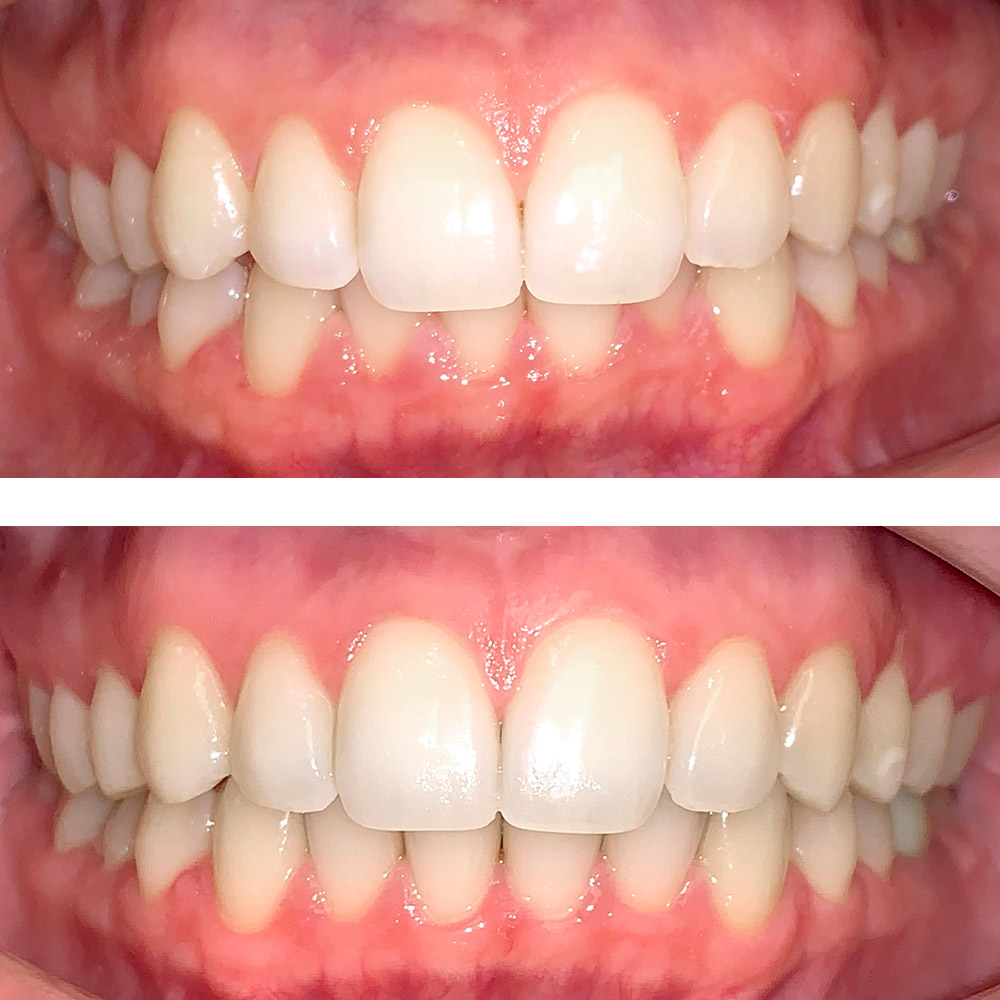

Кейс 11

Акинфиева Анна Владимировна

Количество кап ВЧ 12

Количество кап НЧ 16

ДО

ПОСЛЕ